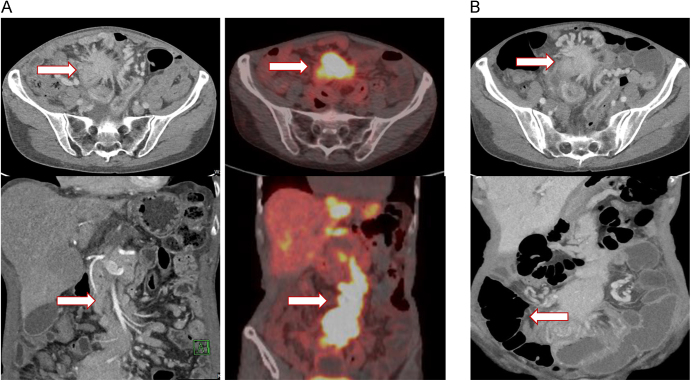

Results: Among the cases reviewed, we identified three patients who developed bowel ischemia/perforation shortly after their initial treatment with 177Lu-DOTATATE. All patients had metastatic small bowel NET with prominent mesenteric mass encasing/obstructing the mesenteric vessels and preexisting symptoms of postprandial abdominal pain.

Conclusion: Acute bowel ischemia may be a rare complication of PRRT in patients with mesenteric arterial or venous obstruction from mesenteric metastasis.